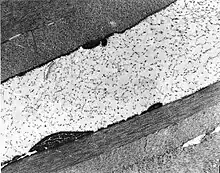

Congenital stromal dystrophy. Transmission electron microscopy of the corneal stroma showing normal collagen lamellae separated by abnormal randomly distributed collagen filaments in an electron-lucent extracellular matrix.

Congenital stromal corneal dystrophy (CSCD) is an extremely rare, autosomal dominant form of corneal dystrophy.[1] Only 4 families have been reported to have the disease by 2009.[2] The main features of the disease are numerous opaque flaky or feathery areas of clouding in the stroma that multiply with age and eventually preclude visibility of the endothelium. Strabismus or primary open angle glaucoma was noted in some of the patients. Thickness of the cornea stays the same, Descemet's membrane and endothelium are relatively unaffected, but the fibrils of collagen that constitute stromal lamellae are reduced in diameter and lamellae themselves are packed significantly more tightly.